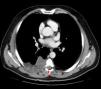

Observación clínicaVarón de 52años, sin antecedentes de interés, con dolor torácico dorsal de 6meses de evolución. Al no mejorar la clínica del paciente, se optó por la realización de una resonancia magnética (RM), previa radiografía de tórax normal. El diagnóstico fue de hidatidosis costal con extensión intrarraquídea (fig. 1). Ante la duda de la naturaleza de dicho proceso, se solicitó una TC toracoabdominal, hallando una masa paravertebral derecha de 88×60×95mm de predominio quístico y contornos lobulados, morfología extrapleural e introducción por el orificio foraminal derecho entre el sexto y el séptimo arcos costales hacia el canal medular, extendiéndose en localización paravertebral desde el cuarto hasta el séptimo arcos costales posteriores derechos, afectando la grasa extrapleural y extendiéndose hacia la musculatura dorsal por los espacios intercostales y sin afectación costal. Con todo ello, la nueva sospecha diagnóstica fue de sarcoma de partes blandas (fig. 2). Se realizó una punción-aspiración con aguja fina (no diagnóstica). Dado el hallazgo intrarraquídeo de la masa, se decidió realizar un abordaje combinado neuroquirúrgico y torácico.